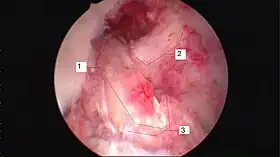

![]() Arthroscopic anterior cruciate ligament (ACL) reconstruction (right knee). The tendon of the semitendinosus muscle was prelevated, folded and used as an autograft (1). It appears through the remnant of the injured original ACL (3). The autograft then courses upwardly and backwardly in front of the posterior cruciate ligament (2). | |